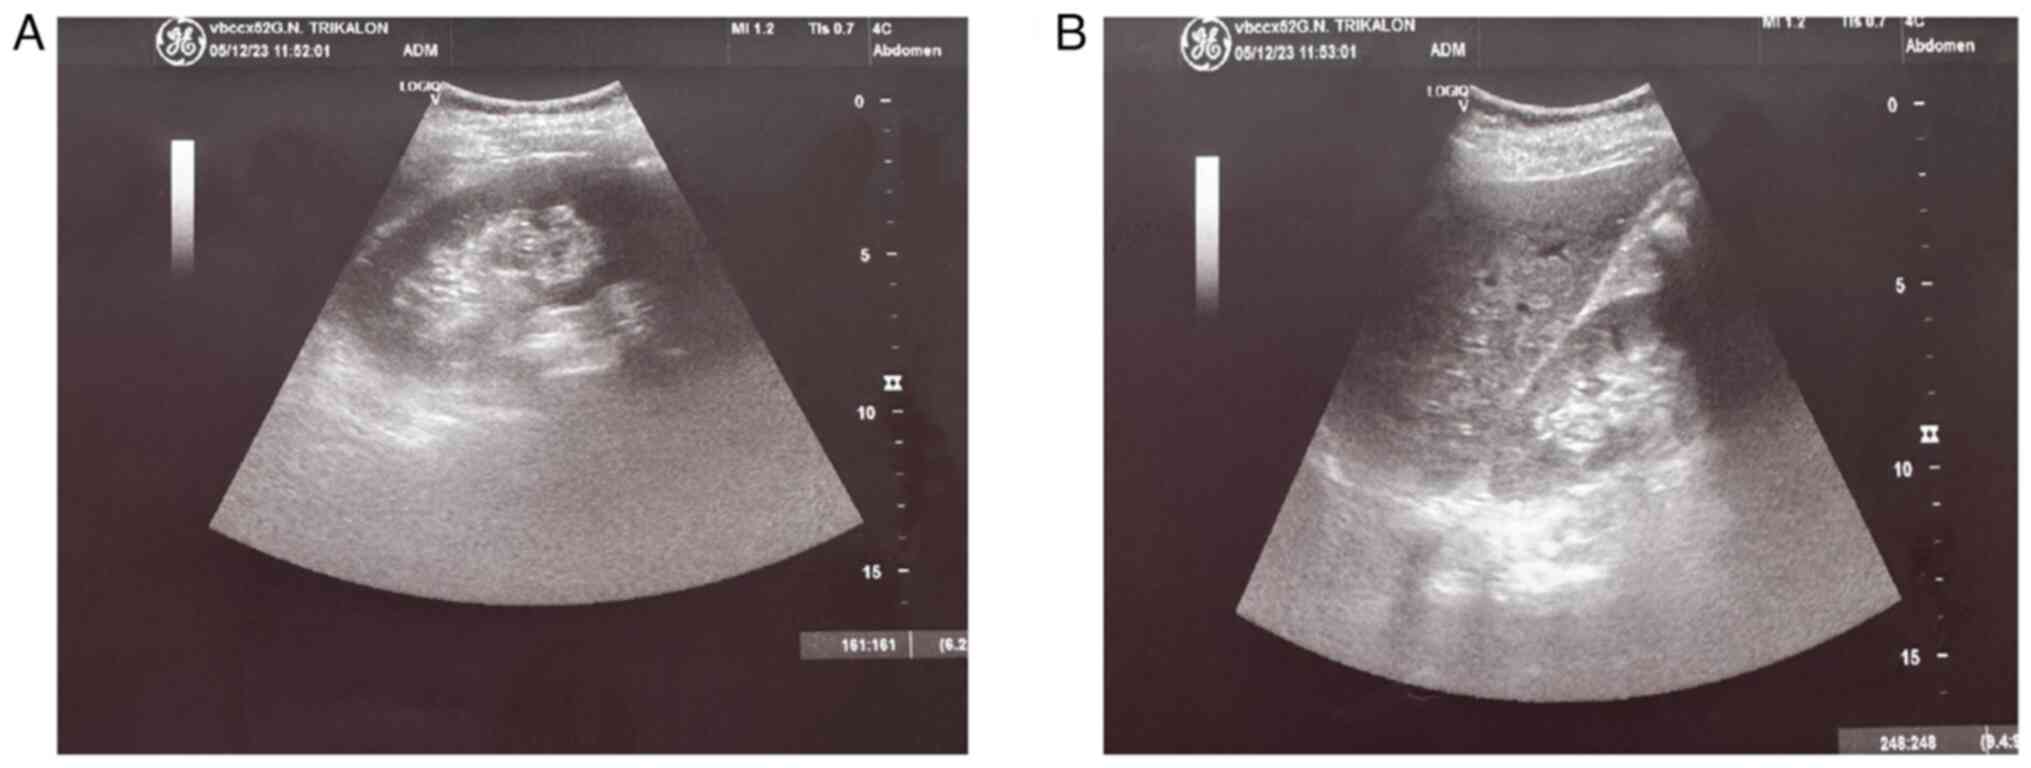

Figure 3

Preoperative ultrasound image of the kidneys revealing bilateral dilatation of the pelvicalyceal system and the upper ureters: (A) Right kidney, (B) left kidney.

Upon a gynecological examination and upon the inspection of the vagina with a speculum, the cervix was not visible. In the upper third of the vagina, in the anatomical position of the cervix, a large solid mass was observed; the position of the external cervical os could not be clearly identified by visual inspection or palpation (Fig. 1). The transvaginal ultrasonographic findings were inconclusive. The scan detected the presence of a large well-circumscribed mass, with a maximum diameter of 10 cm, at the anatomical position of the cervix, raising suspicion of an intracervical leiomyoma (Fig. 2). A renal ultrasound revealed the bilateral dilatation of the pelvicalyceal system and the ipsilateral proximal ureter (Fig. 3). Furthermore, a computed tomography scan was performed, which revealed significant bladder dilatation and internal non-homogeneity of the cervical canal throughout its entire length, measuring 105x95x90 mm. This lesion caused the thinning of the external wall of the cervix and anterior displacement of the bladder. At the same time, it exerted compression on the posterior wall of the bladder, and malignancy arising from the cervix could not be excluded (Fig. 4). Additionally, computed tomography confirmed the dilatation of the pelvicalyceal system bilaterally up to the ureterovesical junction, accompanied by localized renal cortical thinning and lobulated contour of the left kidney. Magnetic resonance imaging was performed to further elucidate the findings of computed tomography. Magnetic resonance imaging revealed marked bladder distention with internal non-homogeneity of the cervical canal and the presence of a lobulated lesion that protruded intracanal with dimensions of 100x85x105 mm (Fig. 5). This finding was attributed to a large intracervical leiomyoma, strongly ruling out the possibility of cervical malignancy. The levels of tumor markers, namely carcinoembryonic antigen, cancer antigen 125, cancer antigen 15-3 and cancer antigen 19-9 were within the normal range.

Post-operative ultrasound image of the kidneys, which shows complete recovery of renal morphology and function: (A) Left kidney, (B) right kidney.